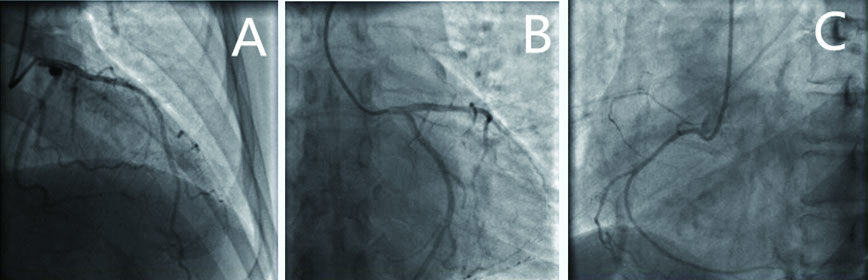

| 图 3 患者冠脉造影结果(示左主干未见狭窄,A为前降支、B为回旋支、C为右冠冠脉光滑,远端血流TIMI3级) |

本例患者为中年女性,有高血压病史,无高血脂、糖尿病、吸烟等危险因素,平素虽无心慌、怕热出汗、进食增多、体质量减少、易激动现象,甲状腺功能示FT3、FT4明显升高,TSH明显降低,甲状腺功能亢进症(甲亢)诊断明确。患者反复发作性胸痛,与劳力无关,发作时呈典型左主干病变心电图改变,心肌损伤标志物明显升高并有动态变化,超声心动图发现节段性室壁运动障碍伴心功能下降,冠状动脉造影结果正常,甲亢合并冠状动脉左主干痉挛(coronary artery spasm,CAS)致急性心肌梗死诊断明确。